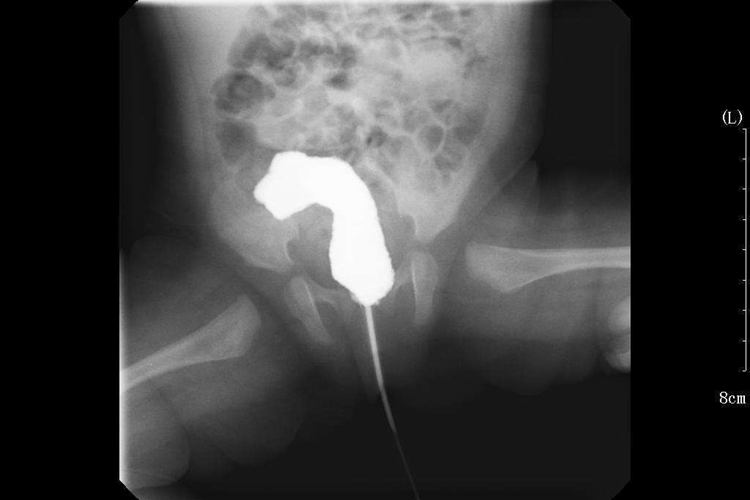

先天性直肠肛门畸形的治疗主要是通过外科手术,重建具有正常控制功能的排便肛门,根据类型和畸形程度,决定不同的手术方法。治疗原则为改善术后排便控制功能,可采用经后矢状入路肛门直肠成形术,或经骶腹会阴肛门成形术,必要时需要联合腹腔镜手术。